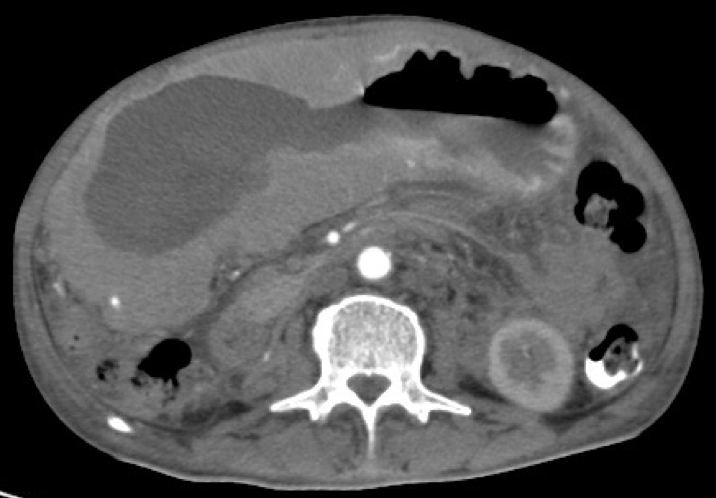

Gastric abnormalities show nonspecific gastrointestinal symptoms and similarly radiological findings. Intra and extra luminal gastric wall thickening are the most common finding in benign and malignant pathologic process. This aim of this case report was to describe several characteristics such as the location and size of the lesion, involvement of the gastric wall and surrounding structures, calcifications, and contrast enhancement pattern which can assist in radiological diagnosis. Several cases at our institution have similar gastrointestinal complaints, however, there were different lesions characteristic found in contrast enhanced abdominal CT scan. The first case 72-years-old man experienced hematemesis with radiologic finding diffuse gastric mucosal thickening as well as homogenous contrast enhancement but without calcification. The second case 37-years-old man complaint dizziness and melena with radiologic finding large tumor more than 10 cm in size, amorph calcification and heterogenous contrast enhancement. The last 60-years-old man case experienced melena and hematemesis, from abdominal CT scan showed irregular gastric mucosal thickening with heterogenous contrast enhancement and fat stranding around the lesion, without calcification. Methods used in these cases were contrast-enhanced abdominal CT scan, esophagogastroduodenoscopy (EGD), and biopsy in order to determine the diagnosis. Contrast-enhanced abdominal CT scan plays a vital role in describing the lesion characteristics which affects the determination of treatment options and future prognosis.